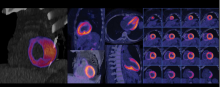

Nuclear imaging technology for both single photon emission computed tomography (SPECT) and positron emission tomography (PET) have made advancements in the past couple years. The main drivers for this have been a movement to digital imaging detectors to improve image quality and address radiation dose concerns, reimbursement and radiotracer supply issues. Other advancements have come in the areas of software to improve image reconstruction quality, offer better clinical qualification and analytics data.